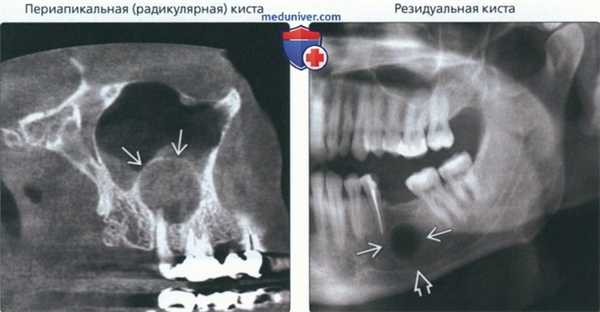

(Слева) На сагиттальной КЛКТ визуализируется большая радикулярная киста, связанная с небным корнем моляра верхней челюсти. Киста приподнимает дно пазухи. Кортикальная пластинка вокруг кисты означает, что киста возникла за пределами пазухи, а не в ней.

(Справа) На кадрированной панорамной рентгенограмме нижней челюсти слева определяется хорошо отграниченное округлое просветление в области, где должны находиться вершины корней отсутствующего первого моляра. Просветление однокамерное и сопоставимо с резидуальной кистой. Обратите внимание, что киста располагается выше нижнечелюстного канала.